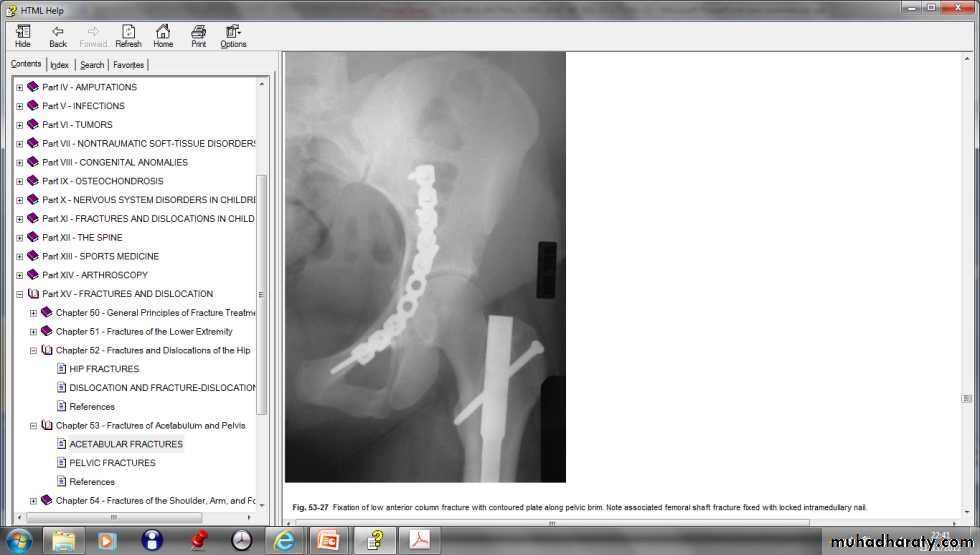

Internal fixation of fracture acetabulum

pelvic_fracture